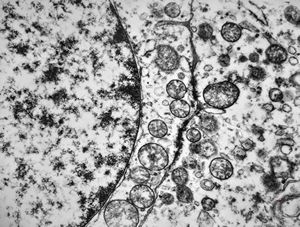

F,50y. | progressive multifocal leukoencephalopathy- viral particles in a glial cell

F,50y. | progressive multifocal leukoencephalopathy- viral particles in a glial cell

F,50y. | progressive multifocal leukoencephalopathy- viral particles in a glial cell